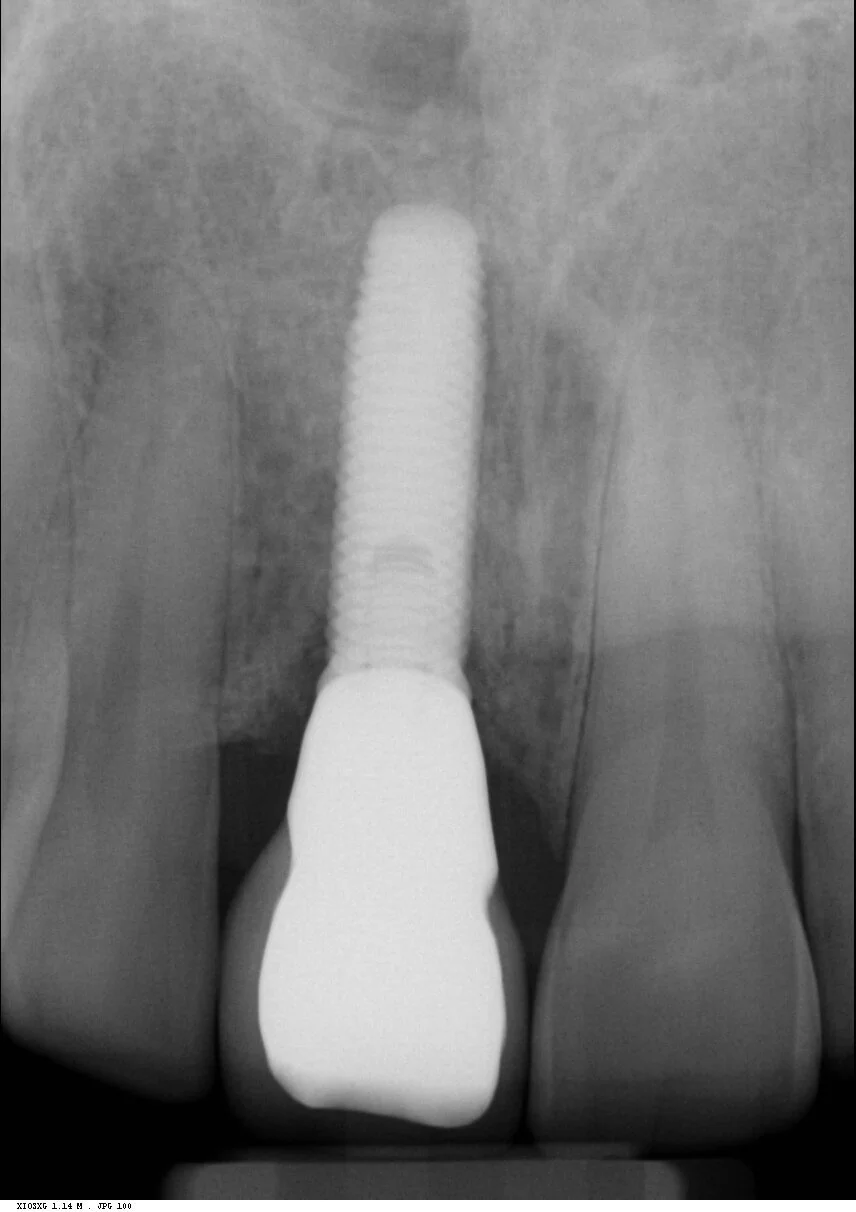

Following a four month post-operative review and confirmation of integration, this implant was then restored with a screw retained integrated abutment / veneered zirconia crown. The crown was then inserted and abutment screw torqued to 35 Ncm. The access cavity was restored with PTFe tape and composite resin. The occlusion was adjusted to ensure light Shim stock hold in ICP, and smooth concave protrusive guidance shared with the neighbouring central incisor.

Reviews carried out at both one year and then six years post operative, showed stable gingival symmetry, and the radiographs showed excellent bone level maintenance.